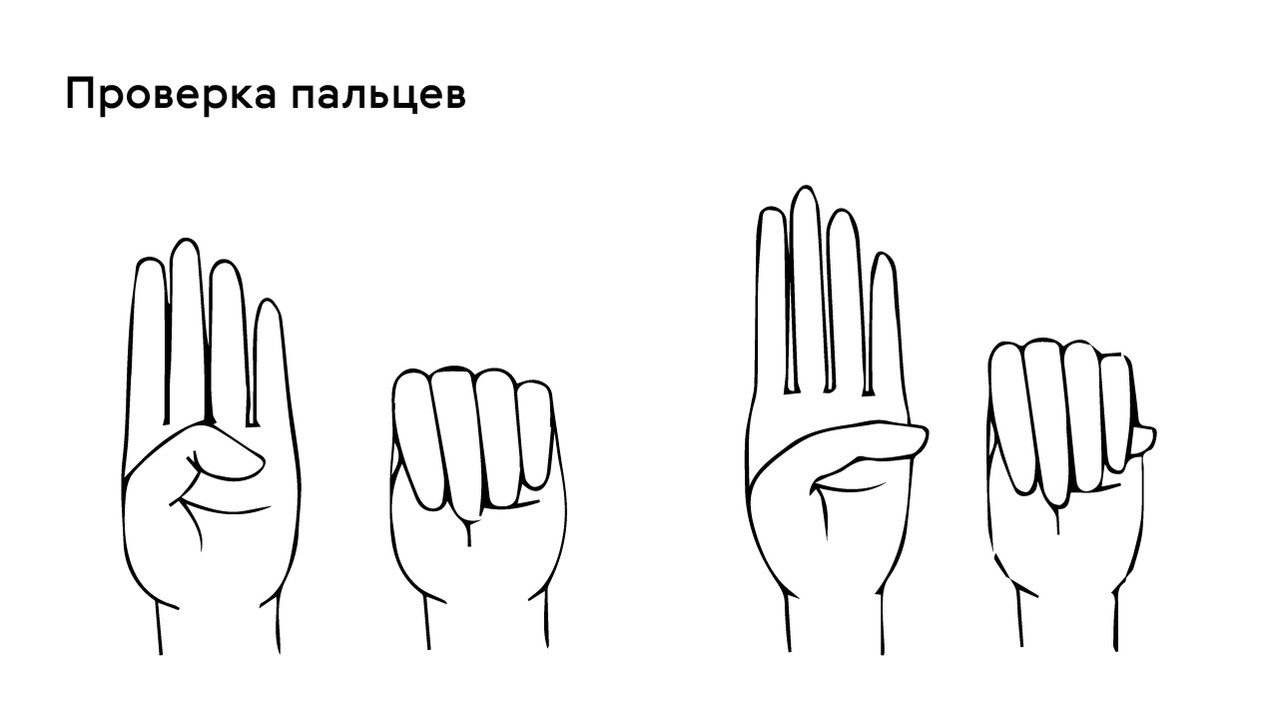

Sindrom marfana tema nauchnoj stati po klinicheskoj medicine chitajte besplatno tekst nauchno issledovatelskoj raboty v elektronnoj biblioteke kiberleninka (Тип файлу jpg)

Sindrom Marfana Tema Nauchnoj Stati Po Klinicheskoj Medicine Chitajte Besplatno Tekst Nauchno Issledovatelskoj Raboty V Elektronnoj Biblioteke Kiberleninka